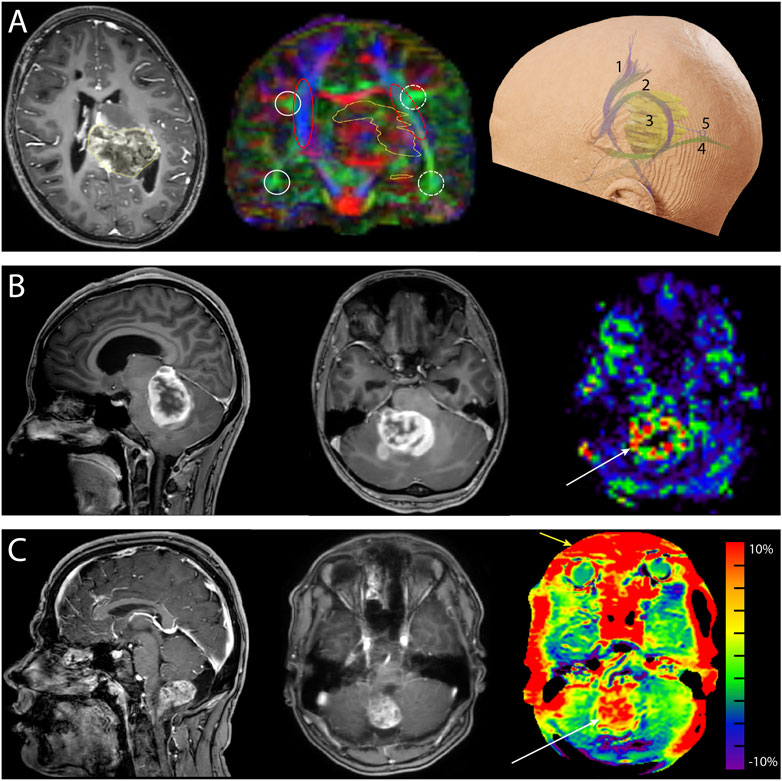

Pediatric cancer relapse prediction is revolutionizing how medical professionals assess the risk of recurrence in young patients, particularly those suffering from brain tumors like gliomas.A recent study by researchers at Mass General Brigham highlights the capabilities of an advanced AI tool that analyzes multiple MRI images over time, offering insights that far surpass traditional methods.

Pediatric brain cancer prediction is revolutionizing the way we approach the diagnosis and management of childhood brain tumors.Recent advancements in artificial intelligence (AI) technology have shown promise in significantly enhancing the accuracy of predicting cancer recurrence, particularly in cases of pediatric gliomas.